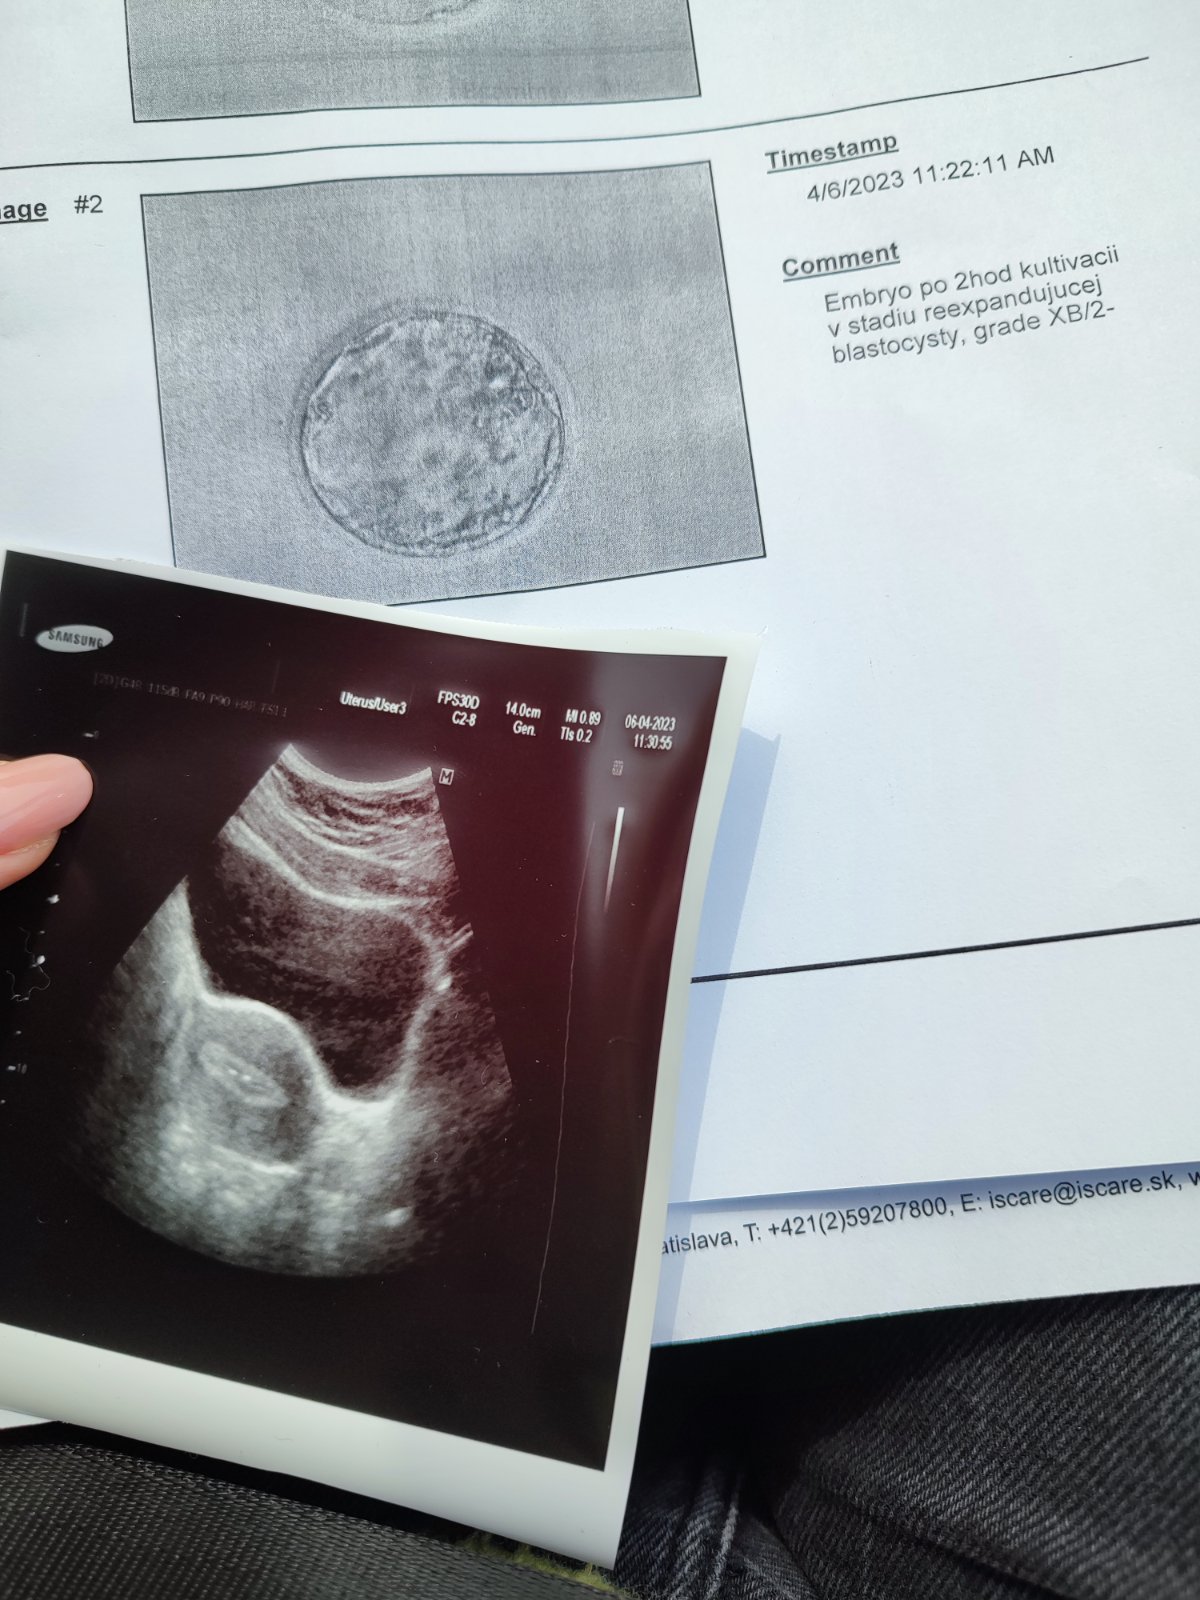

@miskam333 tak bublinky už sú v brušku ❤️❤️

Hatchovali sami takže nebol potrebný asistovanej čo je super

Pani embryilogicka pochválila že všetko vyzerá veľmi dobre

@susan12345 jeeeej super tak to vyzerá ozaj super nádejne 😍určite sa podarí ❤️ ja už mám tiež po no embryjko je horšej kvality ale verím že to zvládne 😊

Aj ja už mám po KET. Embryo má kvalitu 4AA a dali sme aj lepidlo. Držím nám všetkým palce❤️☘️